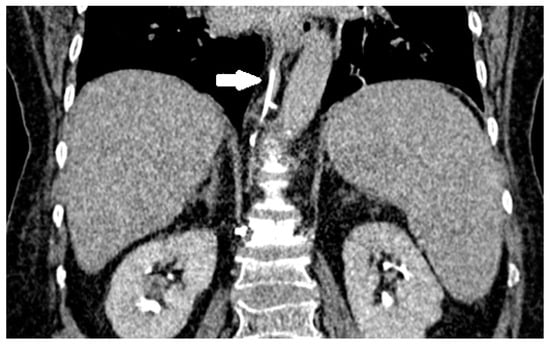

3.4. Venous System Cement Leakage and Pulmonary Embolism